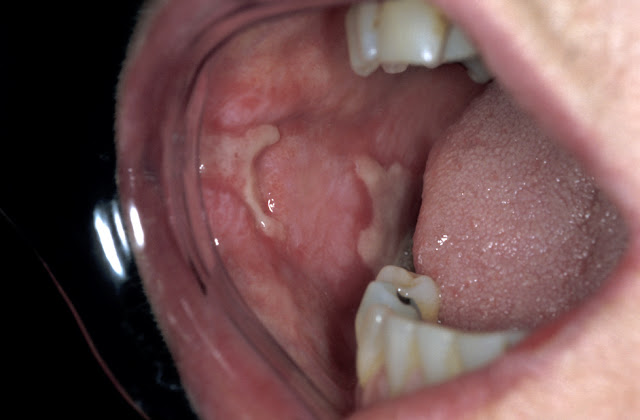

(Bệnh nhân bị tổn thương niêm mạc, khó chịu khi ăn uống)

Viêm miệng do nicotine (nicotinic stomatitis): Là một sự thay đổi ở niêm mạc vòm miệng cứng do hút thuốc quá nhiều, niêm mạc vòm miệng trở nên trắng với các u nhỏ gồ lên, trên đó có các chấm đỏ. Tổn thương này sẽ mất đi sau khi dừng thuốc lá, một số trường hợp hiếm trở thành ung thư biểu mô.